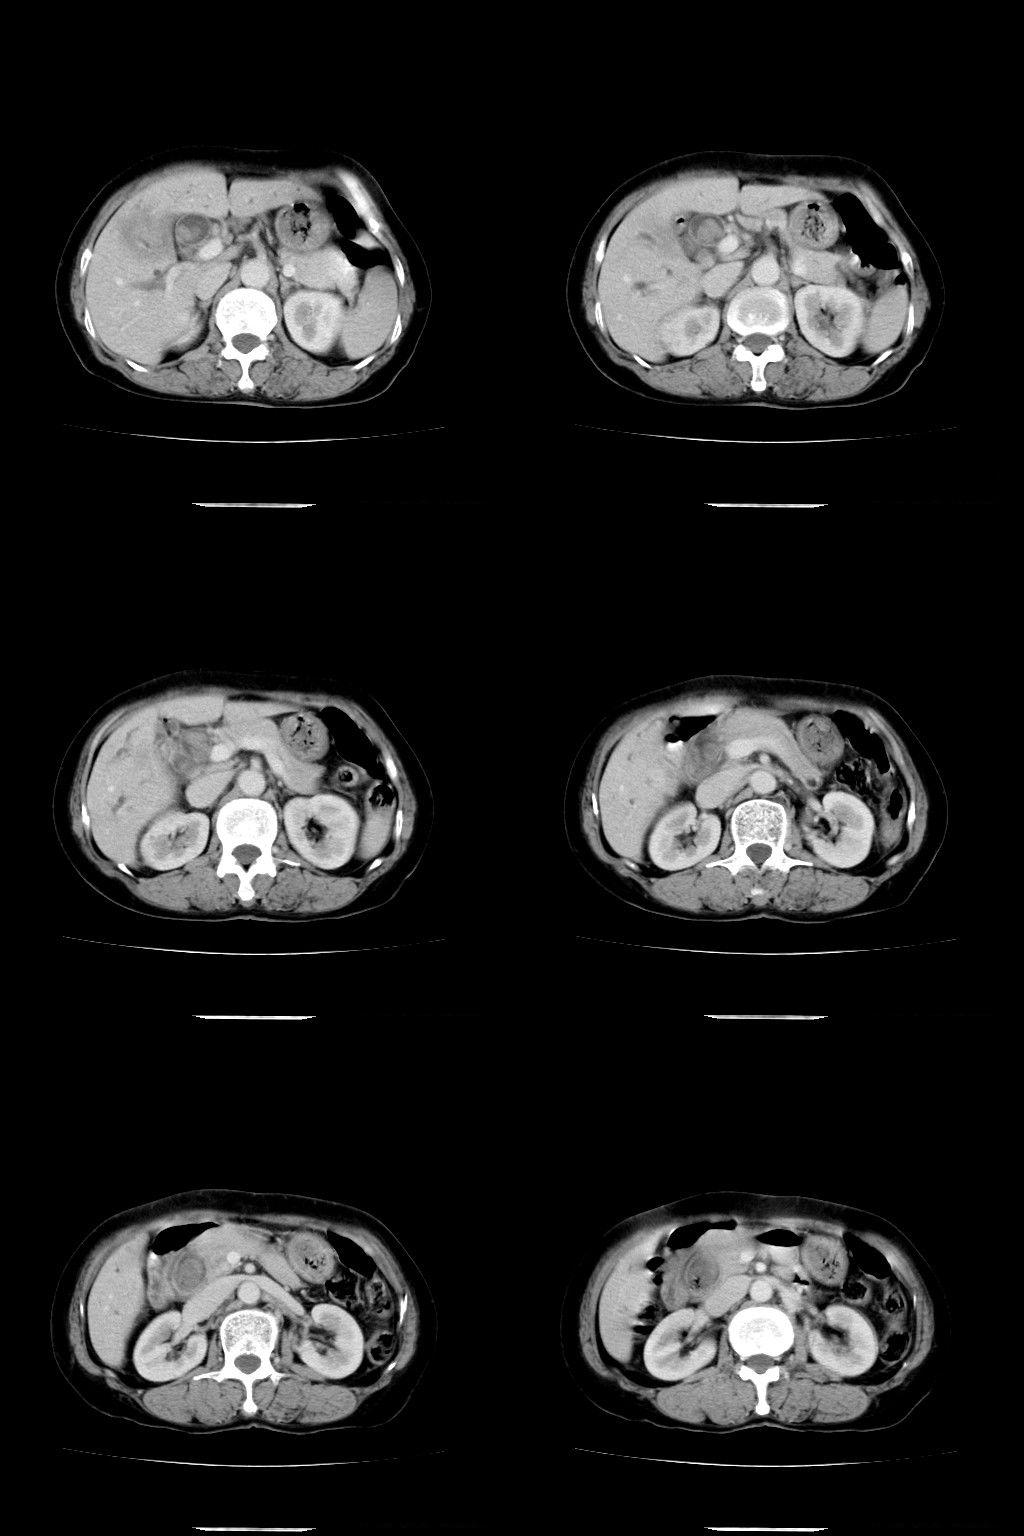

以下是引用随光逐影在2009-1-22 9:27:00的发言:[br]1)考虑胆囊癌侵犯肝脏。2)肝总管及胆总管多发性结石并肝内、外胆管扩张。

以下是引用余辉在2009-1-22 8:49:00的发言:[br]平扫肝内胆管扩张,右肝前叶球形低密度影,边缘较清楚,胆囊壁增厚,内可见较大高密度影,胆总管内亦可见高密度影,胰头区结构欠清。[br]增强动脉期见右肝前叶球形变灶明显增强,边缘见环状低密度区。胆囊见高密度影无增强,胆总管明显扩张,内见块状高密度影,周围环以低密度区,边界清楚。[br]静脉期见右肝前叶病灶持续增强,密度较动脉期增高。[br]考虑1胆囊及胆总管结石伴梗阻性胆系扩张,胆囊胆管炎。[br] 2右肝前叶占位性病变,强化规律符合胆管细胞癌,建议结合其他检查协诊